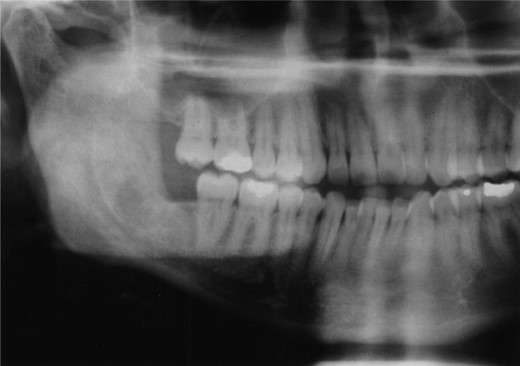

Radiographic examination over the following few months showed new bone formation and within 9 months of the initial biopsy the drain was expelled by formation of new bone (Fig. 3). One year after the commencement of treatment the patient was admitted for enucleation of the cystic remnant. At the time of this procedure a small cyst was removed from the right upper ramus and condylar neck, together, with a separate cyst associated with the lower right wisdom tooth. The patient made an uneventful post-operative recovery and histology revealed two KCOTs with a thick parakeratinized type of epithelium typical of radicular cysts.

Demonstrates bony infill with the nasopharyngeal tube in place.